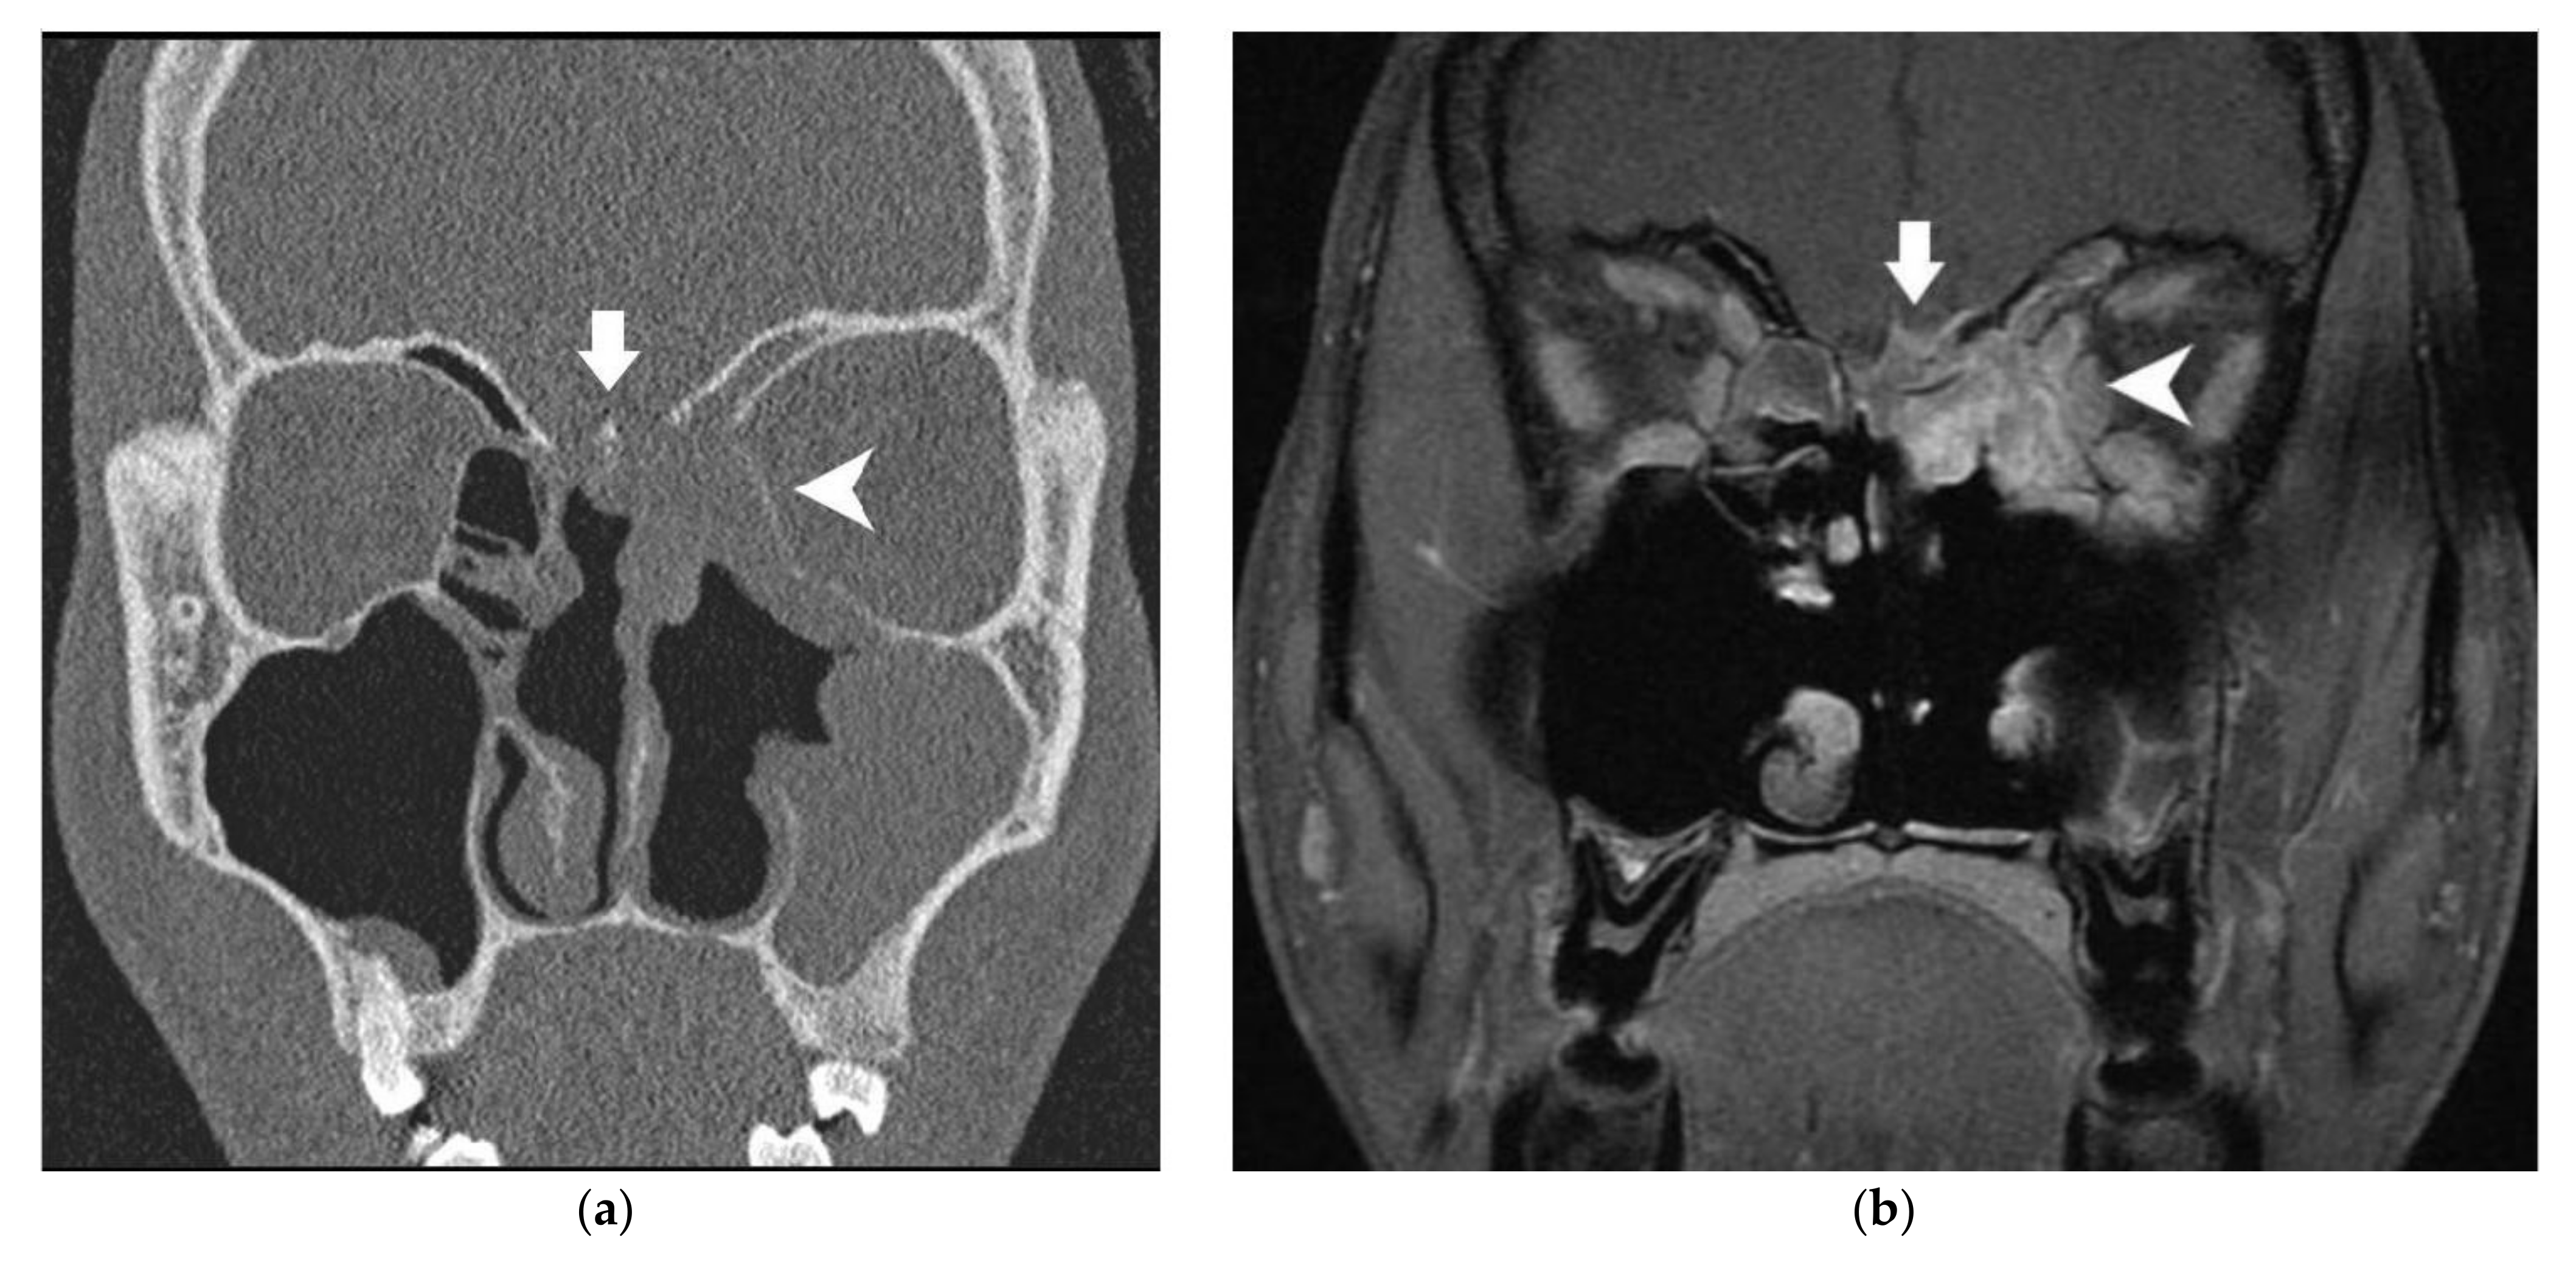

| Bony skull base | CT scanner | Contact without bony modification Minor (<2 mm) erosion Major (≥2 mm) erosion | Free Invaded |

| MRI | Minor (<2 mm) modification Major (≥2 mm) modification | ||

| Bony skull base | CT scanner | Contact without bony modification | 41 | 7.3% (1.5–19.9) | 0.87 | |

| Minor erosion | 32 | 50.0% (32.7–67.3) | ||||

| Major erosion | 54 | 77.8% (66.7–88.9) | ||||

| MRI | Minor modification | 40 | 45.0% (29.6–60.4) | 0.85 | ||

| Major modification | 45 | 88.9% (79.7–98.1) | ||||